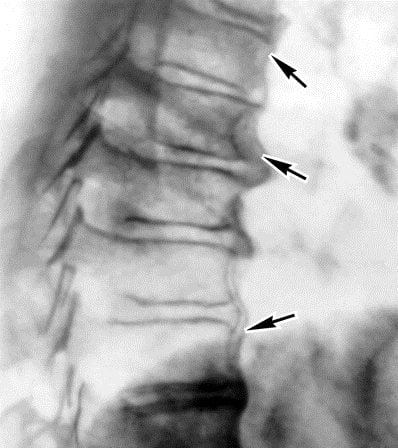

Диагностику болей позвоночника в середине спины начинают с общего осмотра и сбора анамнеза. После этого специалист назначает необходимые исследования. На начальном этапе диагностики обычно ограничиваются рентгеном и общими анализами крови и мочи.

Для исключения серьезных патологий следует сделать рентген.

Диагноз ставится по результатам КТ, МРТ, осмотра и пальпации пациента, анализа крови и рентгенографии.

Диагностировать грудной остеохондроз можно методами МРТ, КТ и рентгенографией. Пока заболевание находится в острой форме, больному назначаются противовоспалительные нестероидные препараты, глюкокортикостероиды, миорелаксанты для снятия болевого синдрома, устранения воспалительного очага и отечности тканей. Для нормализации работы суставов врач пациенту назначает хондропротекторы.